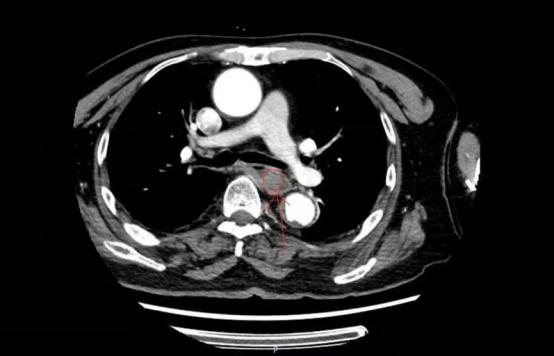

第二天一早,消化内一科主任任珺与乔雪静一起查看了患者的情况,急查了食道增强CT,可见食管内高密度影,考虑有异物。医疗小组人员经详细的病例讨论,决定进行内镜下食道异物取出术。

食道增强CT结果显示食管内高密度影。